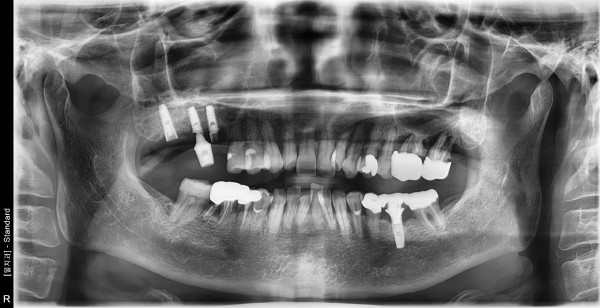

67세 여자 상악 양측 상악동거상술